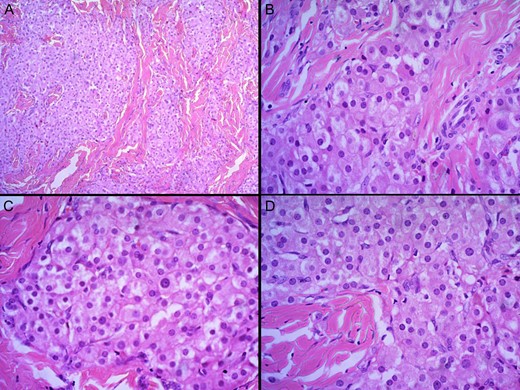

Special stains with Mason trichrome did not show Reinke crystals. The cells displayed diffuse cytoplasmic positivity for synaptophysin (Fig. 3). Thus, the histopathological analysis was more in favour of TART rather than Leydig cell neoplasm.

Staining with synaptophysin under ×40 showing diffuse cytoplasmic positivity.

Histopathologically, TARTs are similar to adrenocortical tissue [6]. They appear as large polygonal cells with abundant eosinophilic cytoplasm arranged in strands or cords separated by fibrous septae. Certain features may help to differentiate TART from Leydig cell tumours. Features such as lack of cytological atypia, low mitotic activity, dense fibrous septa, lymphoid aggregates, adipose metaplasia and prominent lipochrome pigment are more in favour of TART. Reinke crystals are confirmatory of Leydig cell tumours, but is found only in 25–40%. Reinke crystals are absent in TART. Immunohistochemically, diffuse and strong positivity for CD56, negative reactivity for the androgen receptor and focal or diffuse strong reactivity for synaptophysin are noted in TART. On the contrary, weak or negative reactivity for CD56, positive reactivity for the androgen receptor and focal weak or negative reactivity for synaptophysin are demonstrated in Leydig cell tumours [2, 7].

In this case report, the presence of bilateral disease with lack of cytological atypia, low mitotic activity, dense fibrous septae and lymphoid aggregates in histological analysis and diffuse reactivity for synaptophysin in immunohistochemical analysis were in favour of TART. CD56 was not available in our facility. He was then given a trial of steroids and there was marked reduction in the size of both testes. Thus clinicians should be aware of late presentation of TARTs in males with CAH to avoid misdiagnosis.